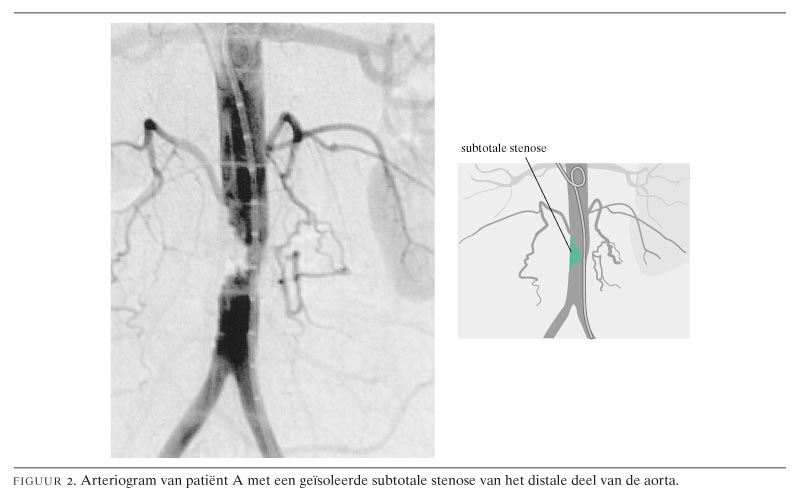

Klinisch denken en beslissen in de praktijk. Een verpleegster met pijn Pijn Links Onder In De Buik Uitstralend Naar De Rug last van rugpijn uitstralend naar lies en buik? pijn in de onderrug en buik is vaak het gevolg van uitstralingspijn. Ontdek de oorzaken en wat je lichaam signaleert. pijn boven in de buik is de meest voorkomende klacht bij chronische alvleesklierontsteking. de pijn onder in uw buik of uw bekken kan er de hele tijd zijn. Pijn Links Onder In De Buik Uitstralend Naar De Rug.